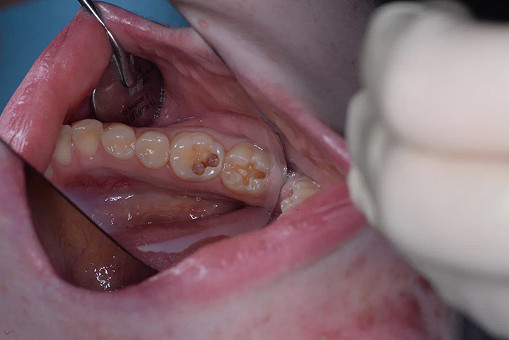

Лечение кариеса проводится следующим образом - сбор анамнеза, проведение местной анестезии, дентальный снимок (при необходимости), изоляция (коффердам), фотопротокол, удаление кариозных тканей (с использованием бора), антисептическая обработка полости, реставрация пломбировочным материалом, шлифовка, полировка.

До/после лечения